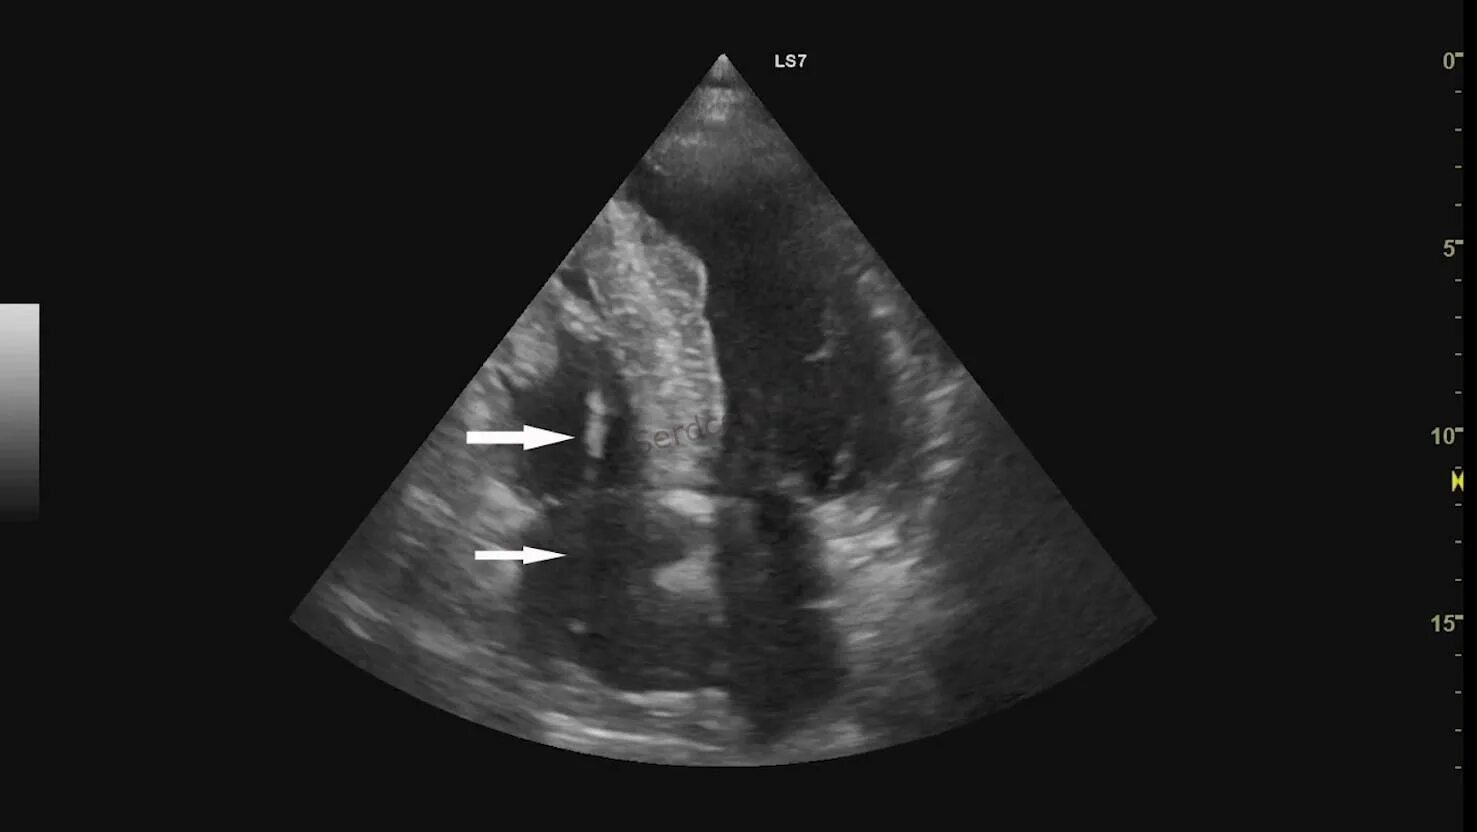

Эхо сердца в туле